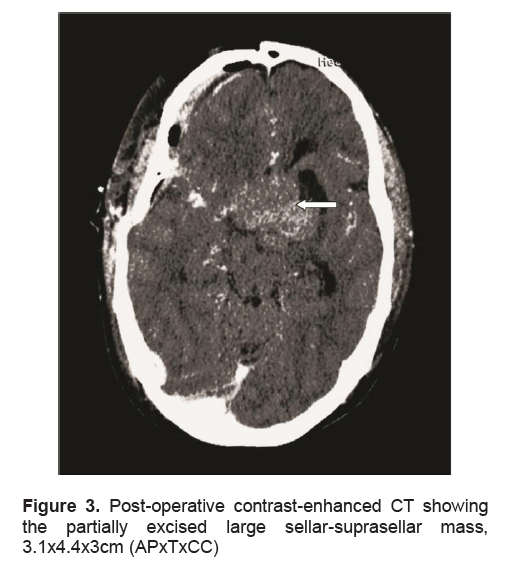

A 38-year-old male presented in another institution because of generalized seizure lasting for 2 minutes. A week prior to the event, the patient complained of generalized weakness, fatigue, anorexia, nausea and vomiting. For the past 5 years, he claimed intermittent episodes of frontal headaches which were later associated with blurring of vision especially at the right lateral area 2 years ago. At the emergency room, the patient was initially man aged as a case of adrenal insufficiency. Precluding hormonal studies, an imaging study was done. Magnetic Resonance Imaging (MRI) of the pituitary revealed a 4.0 x 5.0 x 4.5 cm sellar-suprasellar mass (Figure 1). Cortisol was low at 2.8ug/dl. ACTH was inappropriately normal for a low cortisol. Prolactin was within normal (Table 2). Thyroid function tests revealed elevated total hormones and elevated TSH, but repeat testing using free hormones revealed a low normal FT4 (free T4), a slightly low FT3 (free T3) and still an inappropriately elevated TSH (Table 1). Other hormonal work-ups concluded hypogonadotropic hypogonadism (Table 2). Visual field studies revealed bilateral hemianopsia. Patient was started on steroids (prednisone) and anti-seizure medication (levetiracetam). The symptoms of generalized weakness, fatigue, anorexia, nausea and vomiting resolved immediately after initiating the steroids. This confirmed concluded the diagnosis of adrenal insufficiency secondary to hypopituitarism secondary to a pituitary macroadenoma. The seizure did not recur. A repeat thyroid function test was done a month later which revealed a high normal TSH and an elevated FT4 (Table 1). However, these derangements pointing to a probable central hyperthyroidism were not taken into consideration. Patient eventually underwent craniotomy with excision of the tumor with an aggregate measurement of 3.0 x 2.5 x 0.5cm and a pathological diagnosis of a pituitary adenoma (Figure 2a). Further excision was not possible because its consistency was firm to harn and further excision could further damage some vital tissues. Perioperative course was uneventful. Post-operative CT-scan revealed a residual mass measuring 3.1 x 4.4 x 3.0 cm (Figure 3). Succeeding follow-ups were done in our institution. Patient denied recurrence of the initial symptoms except for the blurring of vision at the right lateral area, although he claimed improvement.

Figure 3. Post-operative contrast-enhanced CT showing the partially excised large sellar-suprasellar mass, 3.1x4.4x3cm (APxTxCC)